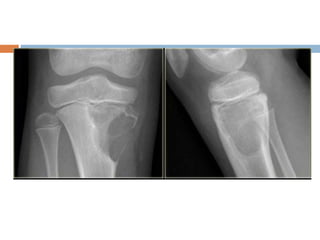

Chondroblastoma

 Benign tumor of immature cartilage

 Occurs primarily in the epiphysis

 Usually proximal humerus, femur or tibia

 Age– around the end of growth period or in

early adult life

 Male predilection

Diagnosis

Rounded, well demarcated radiolucent area in the epiphysis

No central calcification

Sometimes the lesion extends across the physeal line

Occasionally the articular surface is breached